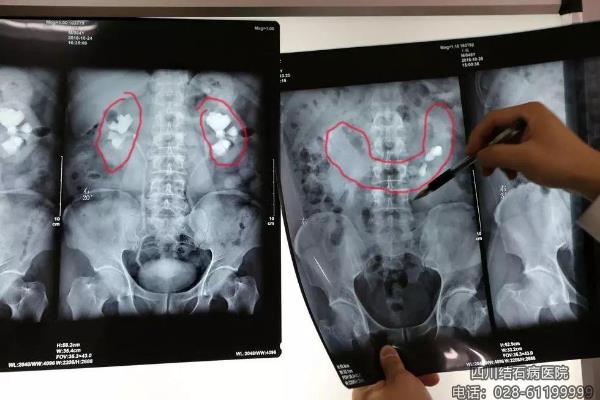

患者王先生的馬蹄腎X光片(右)與正常腎臟(左)的對(duì)比

王先生所拍的X光片